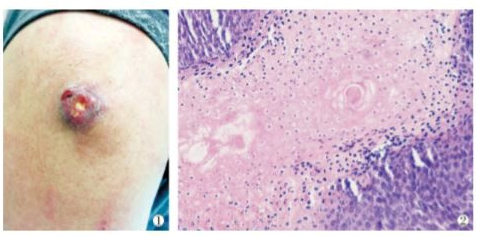

如腫物位於皮內或皮下,通常單發,偶或多發。罕見情況下,腫瘤呈突出表面界限清楚的暗紅色結節,直徑一般在0.5~3cm大,最大可達7cm,偶爾更大,基底可推動。表面面板外觀正常,偶因位置較深而呈藍紅色,或呈紅色、淡藍色。正因為它的顏色,這種腫物常被誤認為是血管瘤。

“腫物一般隨患兒年齡逐漸增大,不會自行消退,長時間存在或受炎症刺激有感染、化膿及破潰可能。”